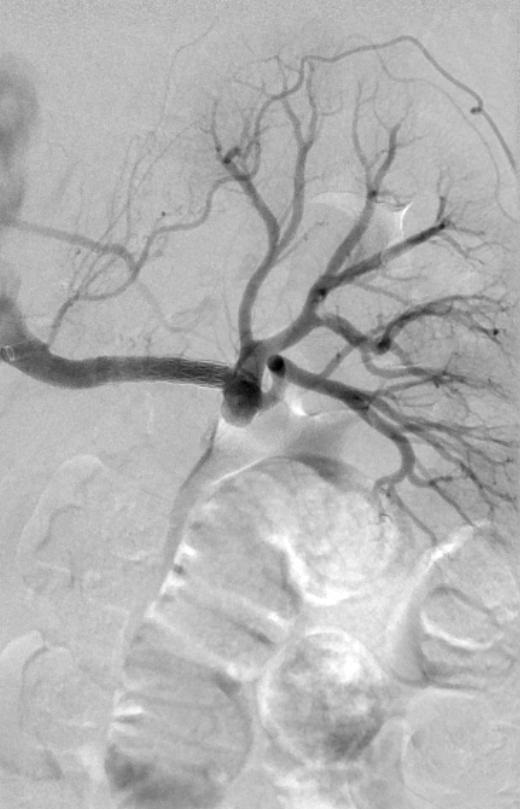

早期弥漫性皮肤系统硬化,手指和面部皮肤增厚。偶然发现肾动脉瘤 治疗技术 技术 - 引导导管在左肾动脉开口 - 将COBRA导管推进到后肾动脉中 - 置换0.35长导丝到远端肾下极动脉 分支痉挛 350mcg 硝酸甘油 右肾下极动脉立即痉挛:硝酸甘油 硝酸甘油部分有效;停

早期弥漫性皮肤系统硬化,手指和面部皮肤增厚。偶然发现肾动脉瘤

治疗技术

技术

- 引导导管在左肾动脉开口

- 将COBRA导管推进到后肾动脉中

- 置换0.35长导丝到远端肾下极动脉

分支痉挛

350mcg 硝酸甘油

右肾下极动脉立即痉挛:硝酸甘油

硝酸甘油部分有效;停止手术?更多的肝素?

5 mm x 22 mm 覆膜支撑架

动脉瘤消失

肾下极血流消失

通过包膜的侧支循环血流

没有内脏动脉瘤逆行充盈

最后一次血管扩张药物后